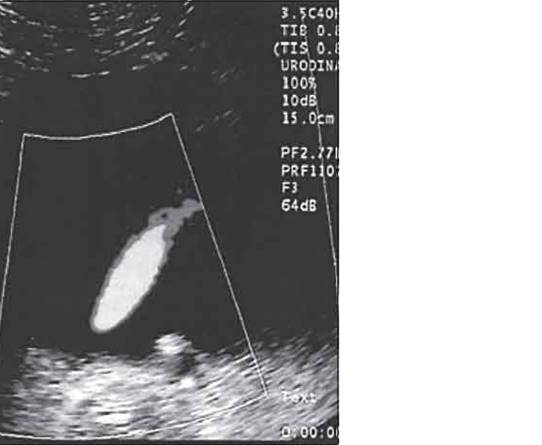

Ехограма розширення порожнинної системи нирки

А – розширення сечоводу:

Б – на тлі сечового міхура.

1 – сечовий міхур, 2 – сечовід

На даній ехограмі спостерігається: зменшення розмірів нирки на стороні поразки; циклічна зміна діаметру сечоводу у верхньому і нижньому відділах; вертикальну спрямованість сечовідно-міхурного викиду, який в нормі має напрям під кутом 30–40° по відношенню до умовної лінії, що сполучає гирла сечоводів.